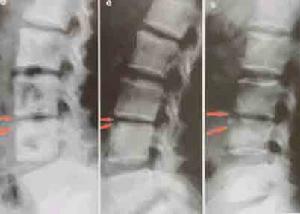

管狀長骨的破壞可表現為不同程度的膨脹變形,脊椎的椎體結核、椎體坍塌可呈楔狀變形,椎體上下之間相互嵌入出現駝背或龜背畸形等。

關節軟骨被破壞可使關節間隙狹窄,軟骨破壞後不會再生,狹窄發生後會長期存在。脊椎椎間盤破壞不能再生,如破壞明顯,椎間隙永久性消失